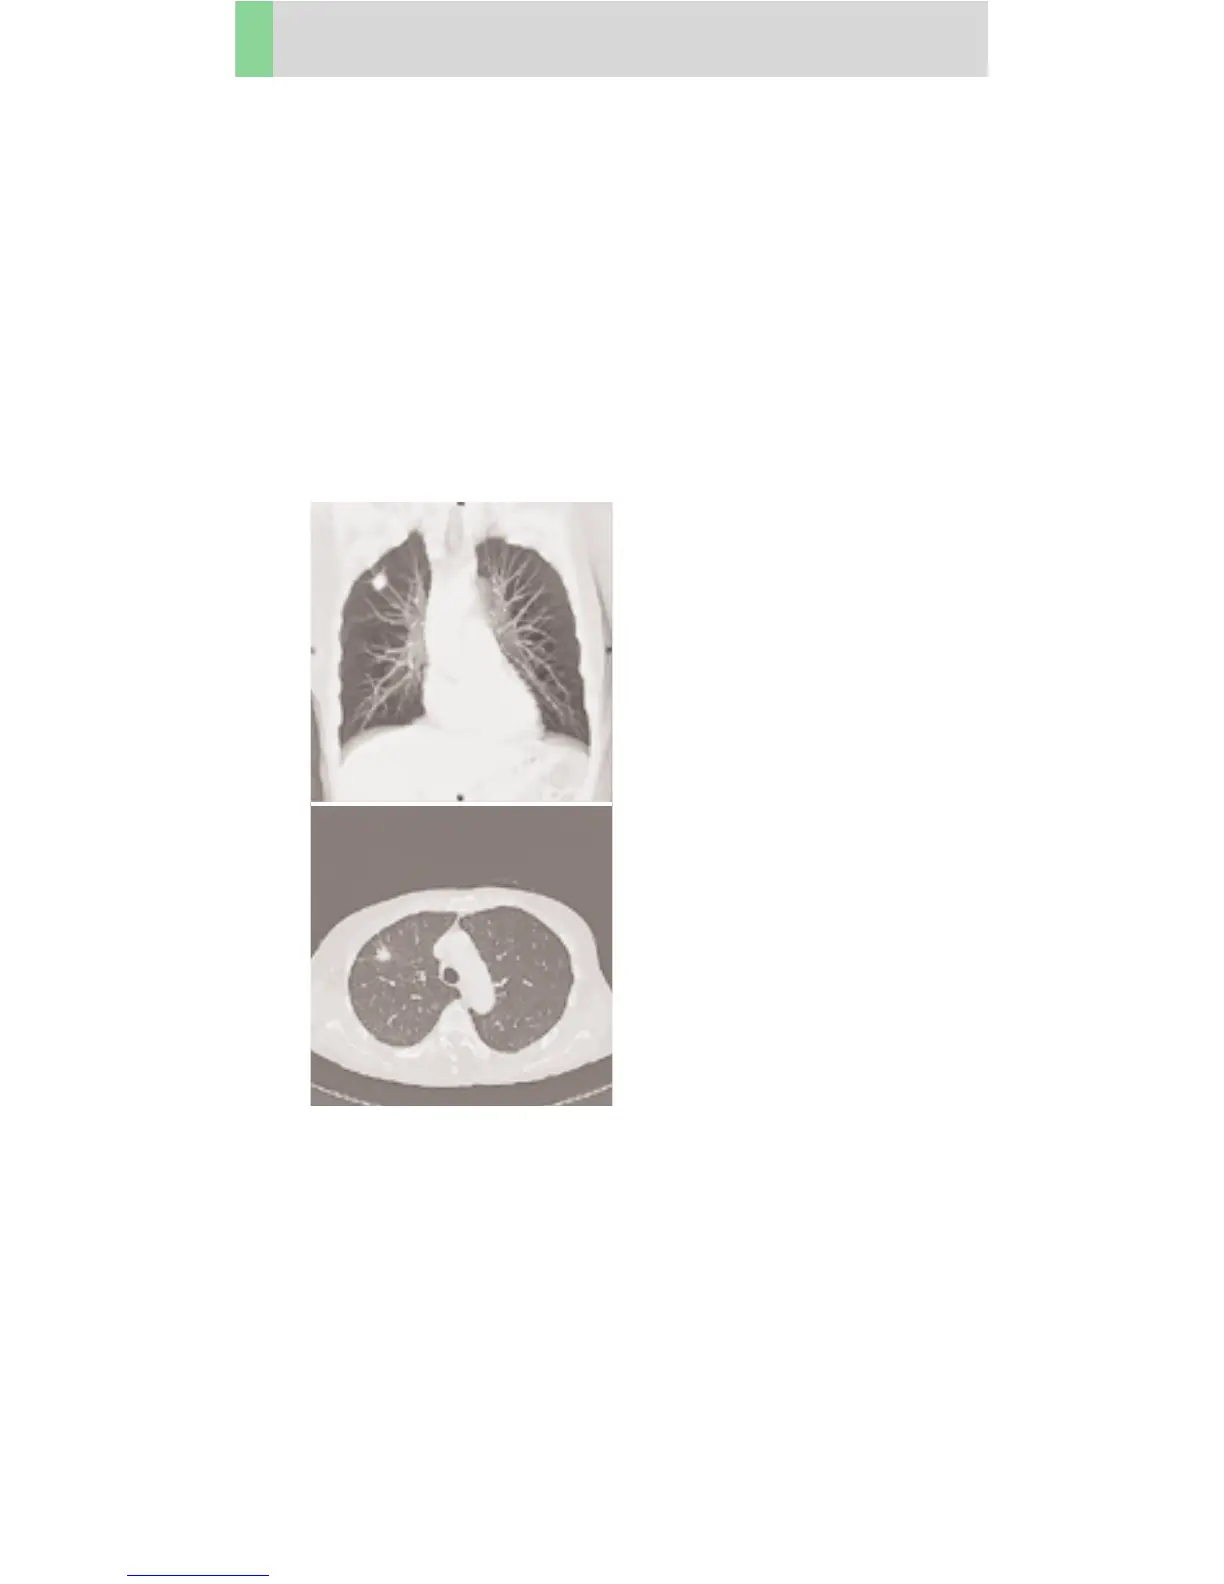

LungLowDose06s

Indications:

Lung studies with low dose setting, e. g. early visuali-

zation of pulmonary nodules, using a 0.6 sec. rotation

time.

A typical thorax study in a range of 30 cm will be

covered in 16.2 sec.